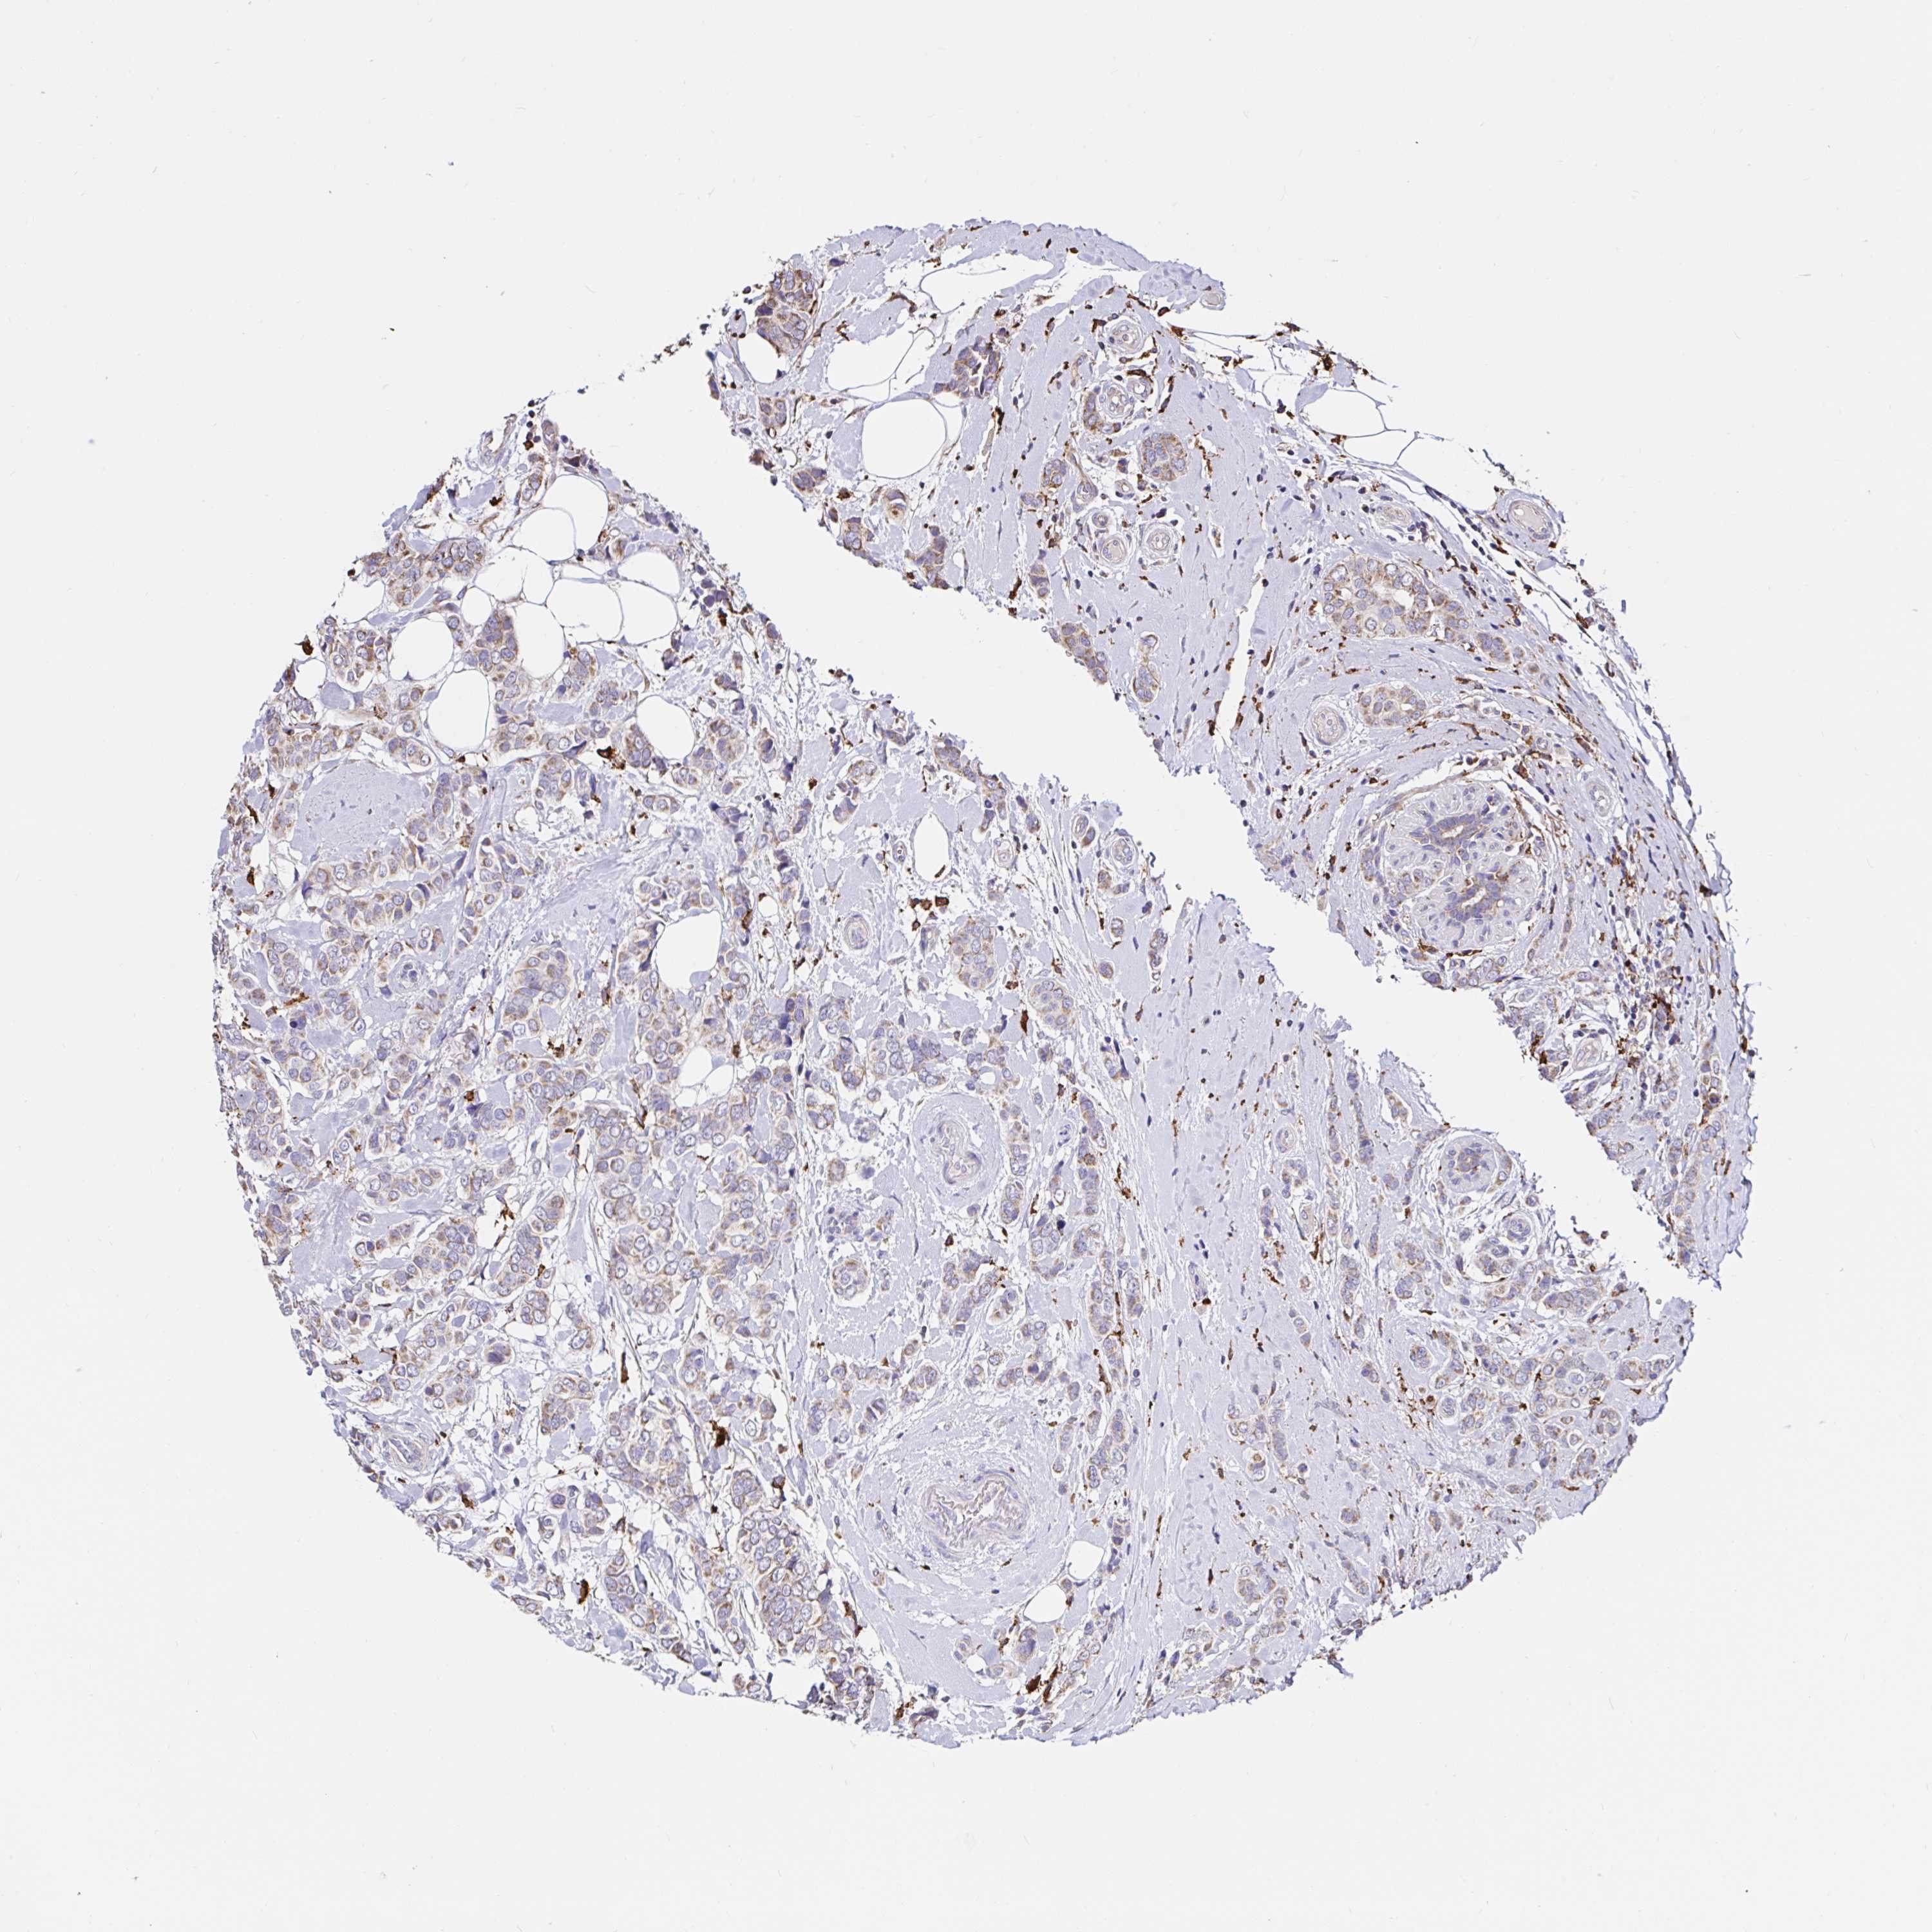

CANCER BREAST CANCER Show tissue menu

BRCA TCGA BRCA VALIDATION PROTEIN EXPRESSION